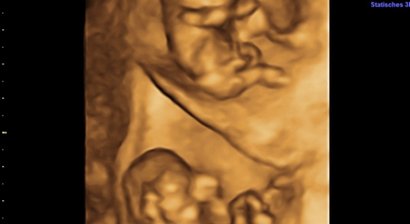

Zwillinge und mehr

Zwillinge, Drillinge und höhergradige Mehrlinge sind natürlich immer ein großes Erlebnis für Eltern, deren Familie und Freunde, aber auch für den Geburtshelfer. Entscheidende Bedeutung für den Verlauf einer Mehrlingsschwangerschaft ist die Ultraschalluntersuchung zwisc...